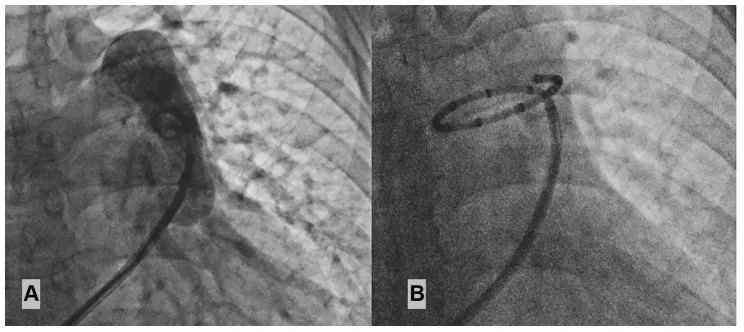

2025年1月15日:患者接受PADN治疗(表1,图1),术后持续口服三联靶向药物治疗。

图1:(A)肺动脉造影,(B)肺动脉去神经射频消融